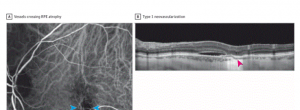

neovascularització coroidal

Direct Visualization of a New Choroidal Vessel...

Direct Visualization of a New Choroidal Vessel on Spectral-Domain Optical Coherence Tomography